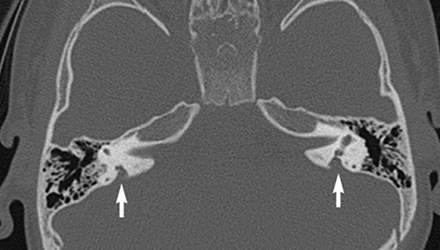

SLC26A4基因定位于人類染色體7q31,SLC26A4基因和大前庭導水管綜合征相關突變位點的發現,證實SLC26A4是大前庭導水管綜合征的責任基因。

我們平時提到的“一巴掌打聾”、“一跤摔聾”其實都與SLC26A4基因突變有關,絕大多數大前庭導水管綜合征都是SLC26A4基因突變惹的禍。

SLC26A4基因編碼一種叫“Pendrin”的跨膜轉運蛋白,在機體離子成分平衡的維持中發揮重要作用。

在內耳,Pendrin表達于內淋巴管、內淋巴囊、橢圓囊、球囊等處,異變的蛋白將對這些結構的正常生理功能產生影響,引發聽損。

SLC26A4基因突變導致的大前庭導水管綜合征的典型表現為兒童時期的聽力損失,90%的患者為雙側性,聽力損失程度不一,可表現為接近正常或重-極重度。

病程可為穩定性、進行性或波動性,聽力可逐步下降至全聾;跌倒、撞擊等行為或無外界影響都可能引發聽力的下降。